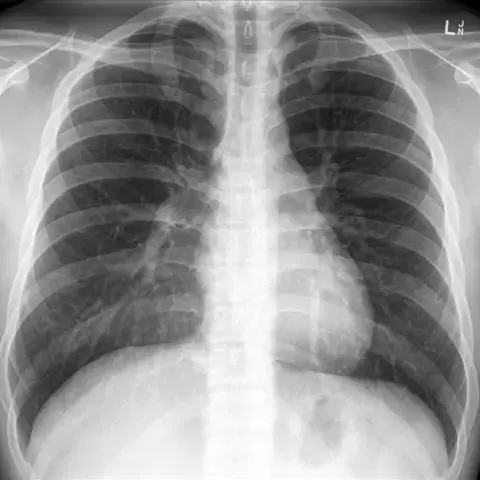

Radiografia do tórax: Anatomia básica simplificada #radiologia